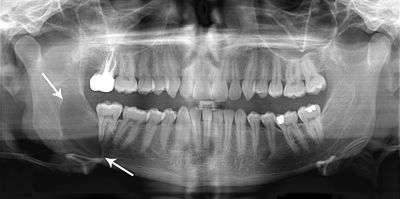

A keratocystic odontogenic tumour (also keratocystic odontogenic tumor, KCOT)[1] is a rare and benign but locally aggressive developmental cystic neoplasm. It most often affects the posterior mandible.

Swelling is the most common presenting complaint; however, KCOTs may be asymptomatic and found incidentally on dental X-rays.[5]

Radiologically

- Odontogenic Myxoma

- Ameloblastoma

- Central Giant Cell Granuloma